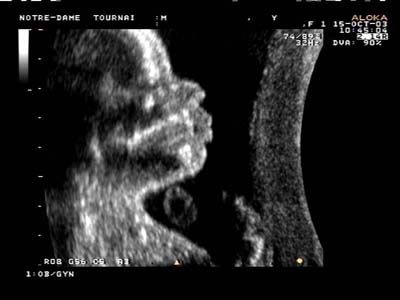

Profil harmonieux